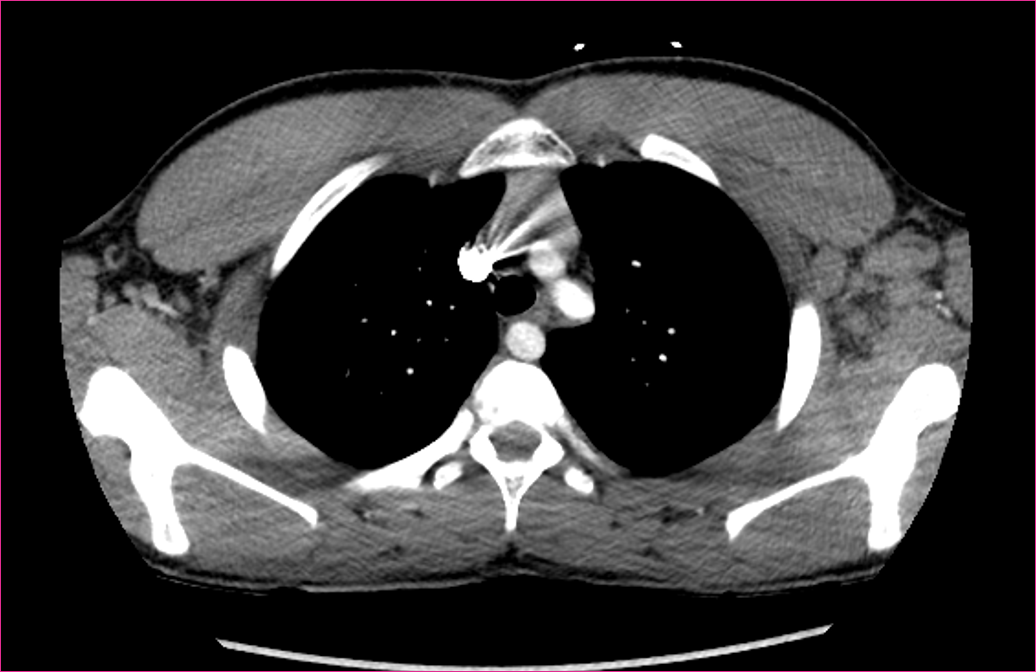

What is your diagnosis?